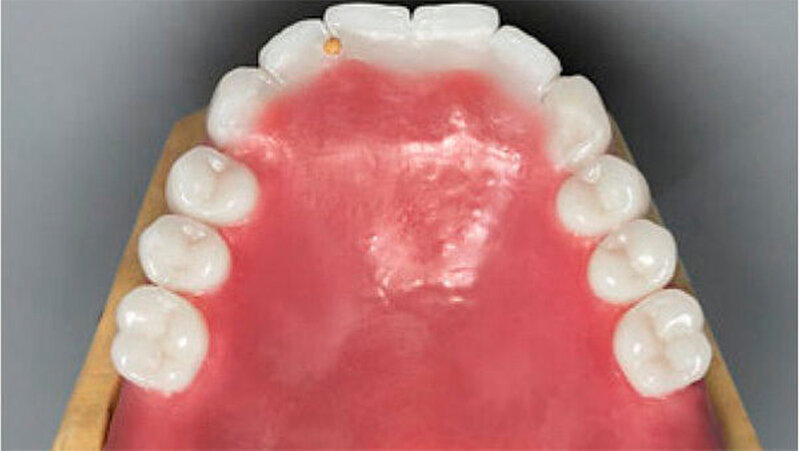

Um die Realisierbarkeit des Therapieziels zu überprüfen, erfolgte im Vorfeld eine diagnostische Aufstellung der Prothesenzähne im Ober- und im Unterkiefer, was eine adäquate Analyse des intra- und intermaxillären Platzangebots ermöglichte (Abb. 8 bis 10). Nun wurden die Pfeilerzähne für die Rekonstruktion mit Teleskopkronen präpariert (Abb. 11). Die individuellen Abformlöffel für die definitive Abformung entsprachen einem Duplikat der diagnostischen Aufstellungen des Ober- und Unterkiefers aus durchsichtigem Kunststoff. Dies ermöglichte gleichzeitig die Montage der Meistermodelle und die Übertragung der Gesamtaufstellung auf das Meistermodell.

Nach Einprobe der Aufstellung der Prothesenzähne in Wachs wurden die Primärteile aus Gold und deren Galvano-Sekundärteile hergestellt. Letztere wurden in die fertige Prothese eingeklebt (Abb. 12 und 13). Auf eine gegossene Gerüstverstärkung wurde aufgrund des ausreichenden Platzangebots und der relativ geringen Kaufkräfte bei dieser, als Übergangsprothese geplanten Arbeit, aus Kostengründen verzichtet. Zur Erhöhung der Bruchzähigkeit erfolgte die Prothesenherstellung mit dem IvoBase® System (IvoBase® Injector, IvoBase® High Impact). Eine zusätzliche Glasfaserverstärkung zur Frakturprophylaxe wurde in den Prothesenkunststoff eingearbeitet.